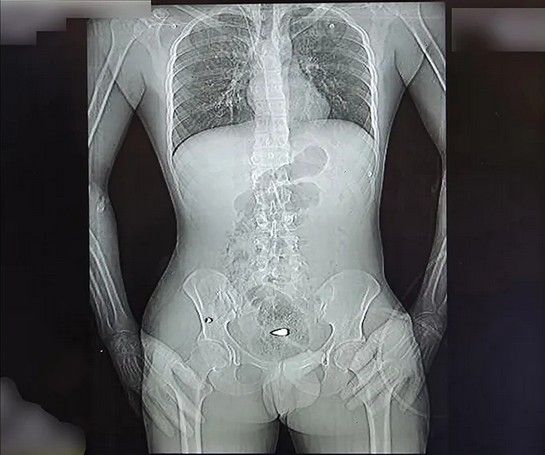

شلیک به اندامهای حیاتی

تصاویر رادیوگرافی و سیتیاسکن نشان میدهد اندام حیاتی تعداد زیادی از معترضان هدف شلیک ماموران امنیتی و نظامی قرار گرفته است. گردن، قفسه سینه، شکم، ستون فقرات و ناحیه تناسلی نقاطی هستند که به کرات هدف تیرهای ساچمهای و گاهی جنگی قرار گرفتهاند. همچنین تعداد زیادی از معترضان تنها از یک ناحیه هدف قرار نگرفتهاند؛ در یکی از موارد تیرهای ساچمهای در سر، گردن، کتف، قفسه سینه، پهلو و لگن فرد بستری دیده میشود. این موارد میتواند حاصل شلیک بیش از یک بار به سمت این معترض باشد. کیانا کثیری در این مورد میگوید که برخی آسیبهای واردشده به این معترض «دائمی» است و تا پایان عمر همراه او خواهد بود.

برخی از معترضان نیز با گلوله جنگی و به شکل مشخص از ناحیه اندام حیاتی هدف قرار گرفتهاند. در یکی از تصاویر رادیوگرافی گلوله یا ترکش در قفسه سینه و در ناحیه ریه مجروح دیده میشود، در تصویری دیگر گلوله جنگی در ناحیه تناسلی یک مرد قرار دارد و در موردی دیگر گلوله در نزدیکی ستون فقرات بیمار ثابت مانده است. کیانا کثیری در مورد عکس آخر میگوید: «در این عکس دو نوع آسیب را مشاهده میکنیم. یکی اصابت ناحیه پشت با گلوله جنگی، بر اساس ورود و قرار گرفتن گلوله به نظر میرسد که گلوله از بالا شلیک شده و آسیب دوم شکستگی سه مهره کمری،Lumbal Columna است که نیاز به ترمیم با فیکسیشنهای ارتوپدی داشته است.»